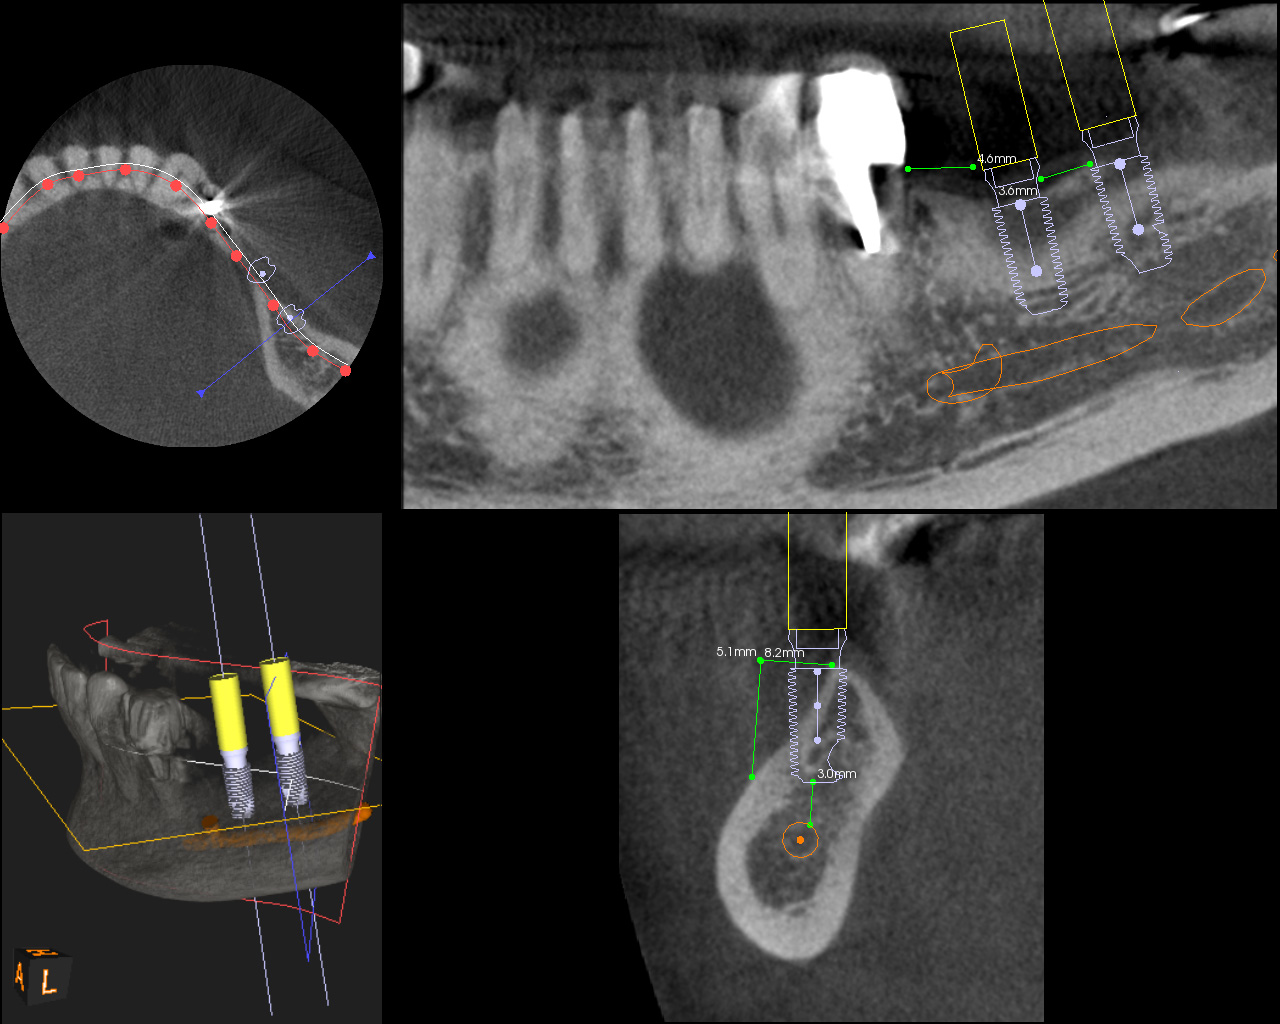

複数の歯に及び歯が失われているためCT画像上で診断と設計を行い、理想的な位置に歯を作ることができるように、サージカルガイドと言われるインプラント手術補助用マウスピースを用いてインプラント手術を行った。

手術の精度を更に上げるサージカルガイド

術前CT

-